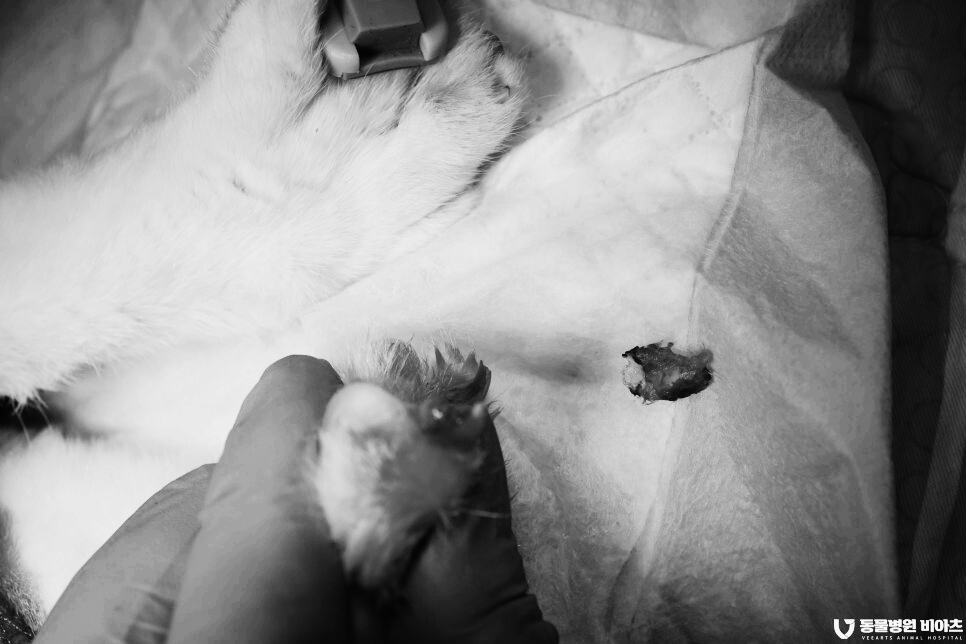

제거된 병변입니다.

치료가 끝난 아이의 발톱입니다.

염증 조직과 변형된 발톱 그리고 육아종까지

깨끗하게 제거를 하였습니다.